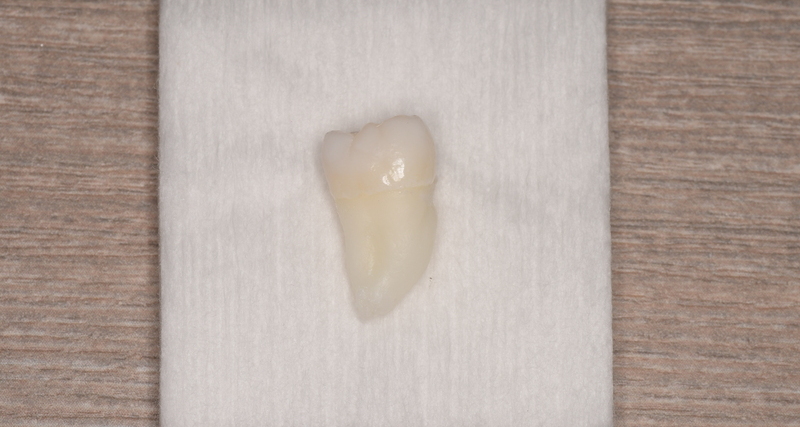

CASE 23

基本情報

| 年齢・性別 | 38歳・男性 |

| 主訴 | 左上親知らずを抜きたい |

| 親知らずのはえ方 | 真っ直ぐはえている |

| 抜歯期間 | 15分 |

| 抜歯費用 | 約2,500円(保険内) (2022年12月現在) |

| 抜歯内容 | 左上の親知らず抜歯 |

| 治療方針 | 親知らずにより頬の内側を噛みやすいということで抜歯しました。 完全に頭がでているため抜歯自体は5分もかからず終わりました。 術後は痛みや腫れも出ていないとのことです。 |

| 特記事項 | 抜歯後は感染をしやすいため、抗生物質を飲み切ってください。 |